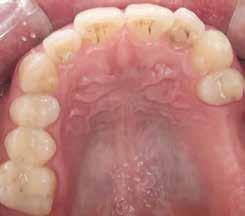

1. a–d. ábra: Műtét előtti állapot mind a négy páciensnél. 1. eset (a). 2. eset (b). 3. eset (c). 4. eset (d).

Az alábbi esettanulmányhoz négy pácienst választottunk ki (1. táblázat). Minden esetben egy, vagy több fog pótlására volt szükség, amelyhez kerámiaimplantátumokat használtunk. Valamennyi páciens általános egészségügyi állapota jó volt.

Vizsgálatok

A pótlásra szoruló fogat, vagy fogakat minden esetben legalább egy évvel a fogpótlást megelőzően eltávolítottuk. Ezen esetek egyikében sem végeztünk alveolus vagy állcsontgerinc prezervációt az eltávolítás során, illetve minden páciens jó szájhigiéniával rendelkezett. Egy kivételével minden páciensnél radiológiai analízist végeztünk CBCT-vel, amelyet

digitális implantátumtervezés követett (SICAT és Sidexis, mindkettő Dentsply Sirona; 1. ábra).